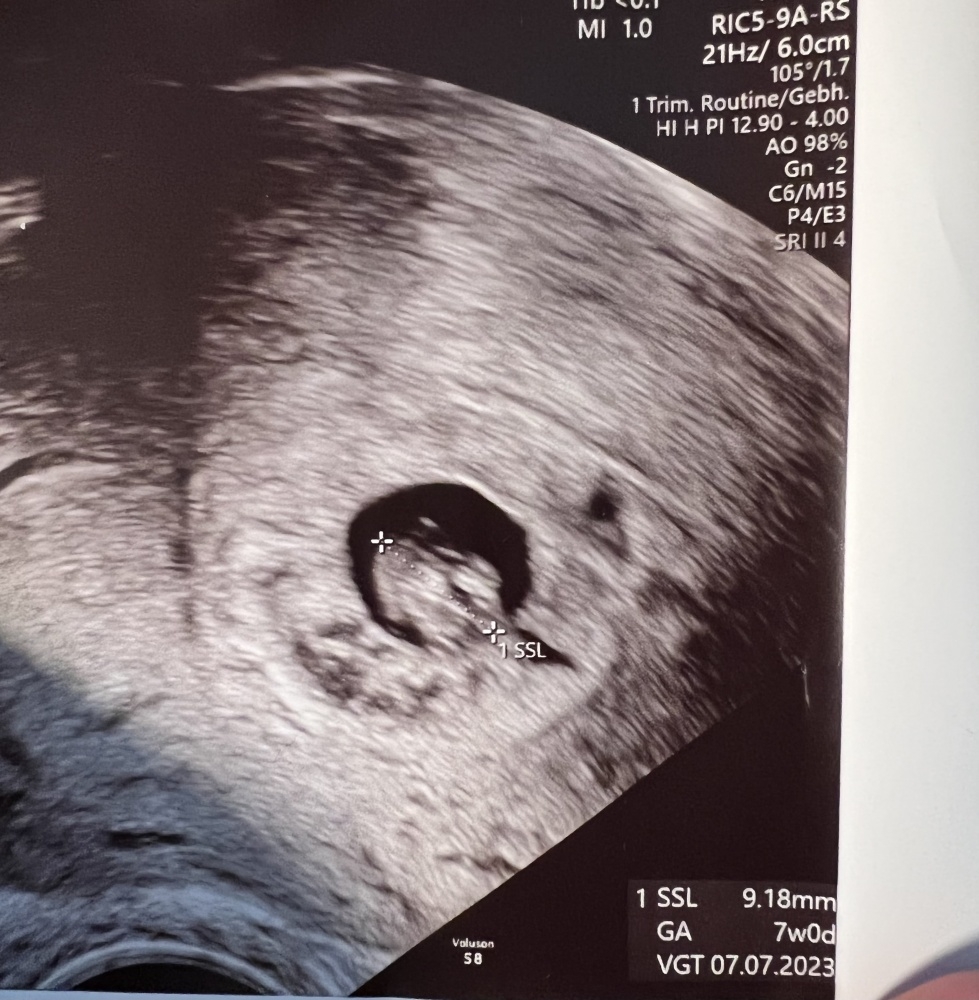

ich kann mein US-Bild vom letzten Freitag auch teilen :) ich war da 7+0… da sieht man die leider kleine Fruchthöhle

vjkhloawtqb4.jpeg

ich hoffe, am Montag ist die Fruchthöhle schon größer und das Herzchen schlägt noch ✊🏻 ich kanns so gar nicht einschätzen, ob es noch da ist oder nicht…